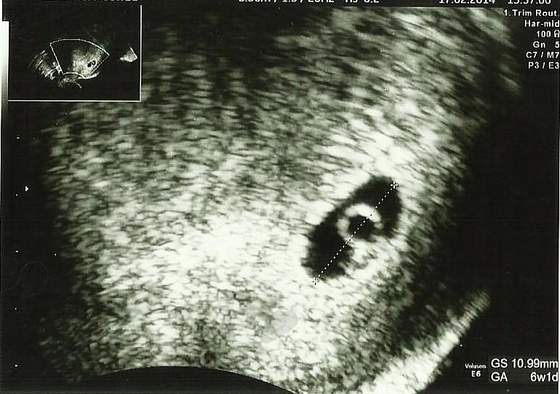

Pani doktor stwierdzila ze jest wszystko super Fasolinka jest duza i silna serducho mocno bije i nic nie wskazuje na to zeby cos moglo byc nie tak:tak: to mnie bardzo cieszy.Wazne ze Maluszek silny i rosnie.

Przedstawiam Wam moje Szczescie :tak: Scan.jpg